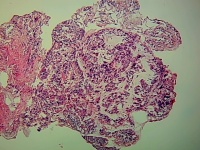

性别年龄22岁临床诊断

一般病史4月前咳嗽,咳痰伴感染。CT:双肺上叶间隔旁肺气肿,右肺中叶内侧段及左肺上叶舌段条索状,右肺中內叶局限性肺不张伴支气管扩张。

标本名称右肺中叶内侧段黏膜

大体所见灰白色小组织2块,直径约0.1CM。

符合支气管扩张病变。

建议:TTF-1;CK7;P53;Syn;CgA;CD56;napsinA;β-catenin等,如有条件,做个基因检测,EGFR;K-ras,以排除腺癌(胎儿型腺癌)的可能性!